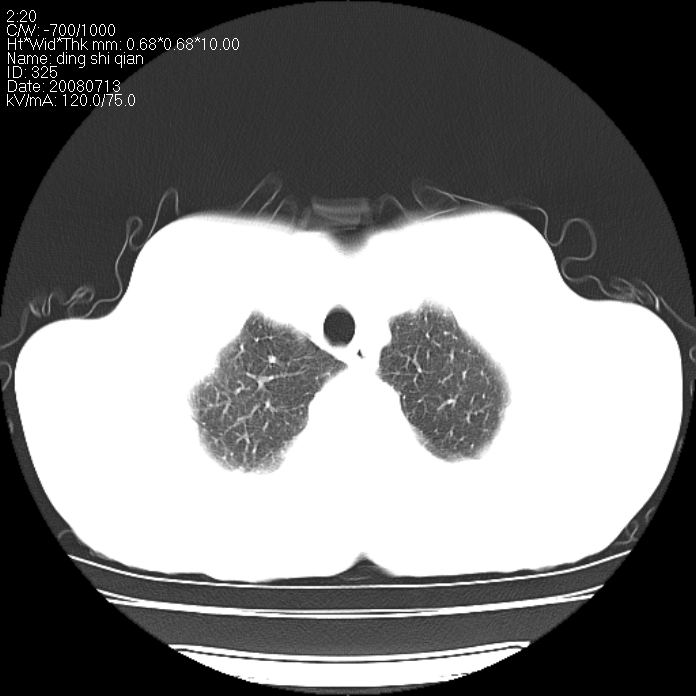

标题: CT14654:男 50岁 近来胸痛 [打印本页]

标题: CT14654:男 50岁 近来胸痛

右侧上肺块状软组织影,浅分叶,边缘毛刺证,与胸膜粘连,考虑:周围性肺癌

右肺上叶周围型肺癌可能性大。